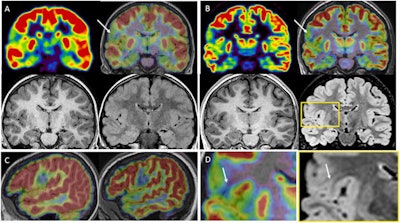

A French group found that PET/MRI with a hybrid scanner was better at identifying target lesions for surgery in epilepsy patients when compared with either approach alone or when PET and MRI images were fused (PET+MRI) together. The approach improved the outcomes of surgery in 40% of patients.

The group found that MRI was initially considered negative in 21 patients. Standalone PET identified abnormalities in 19 cases (76%) and detected four additional structural lesions when fused with MRI imaging. Compared with the fused PET and MRI scans, hybrid PET/MRI sensitivity increased by 13% and identified new structural lesions (mainly focal cortical dysplasias) in six patients (24%).

In addition, hybrid PET/MRI resulted in changes in surgical decisions for 10 patients (40%), consisting of avoiding invasive monitoring in six patients and modifying the planning in four others, the researchers found.